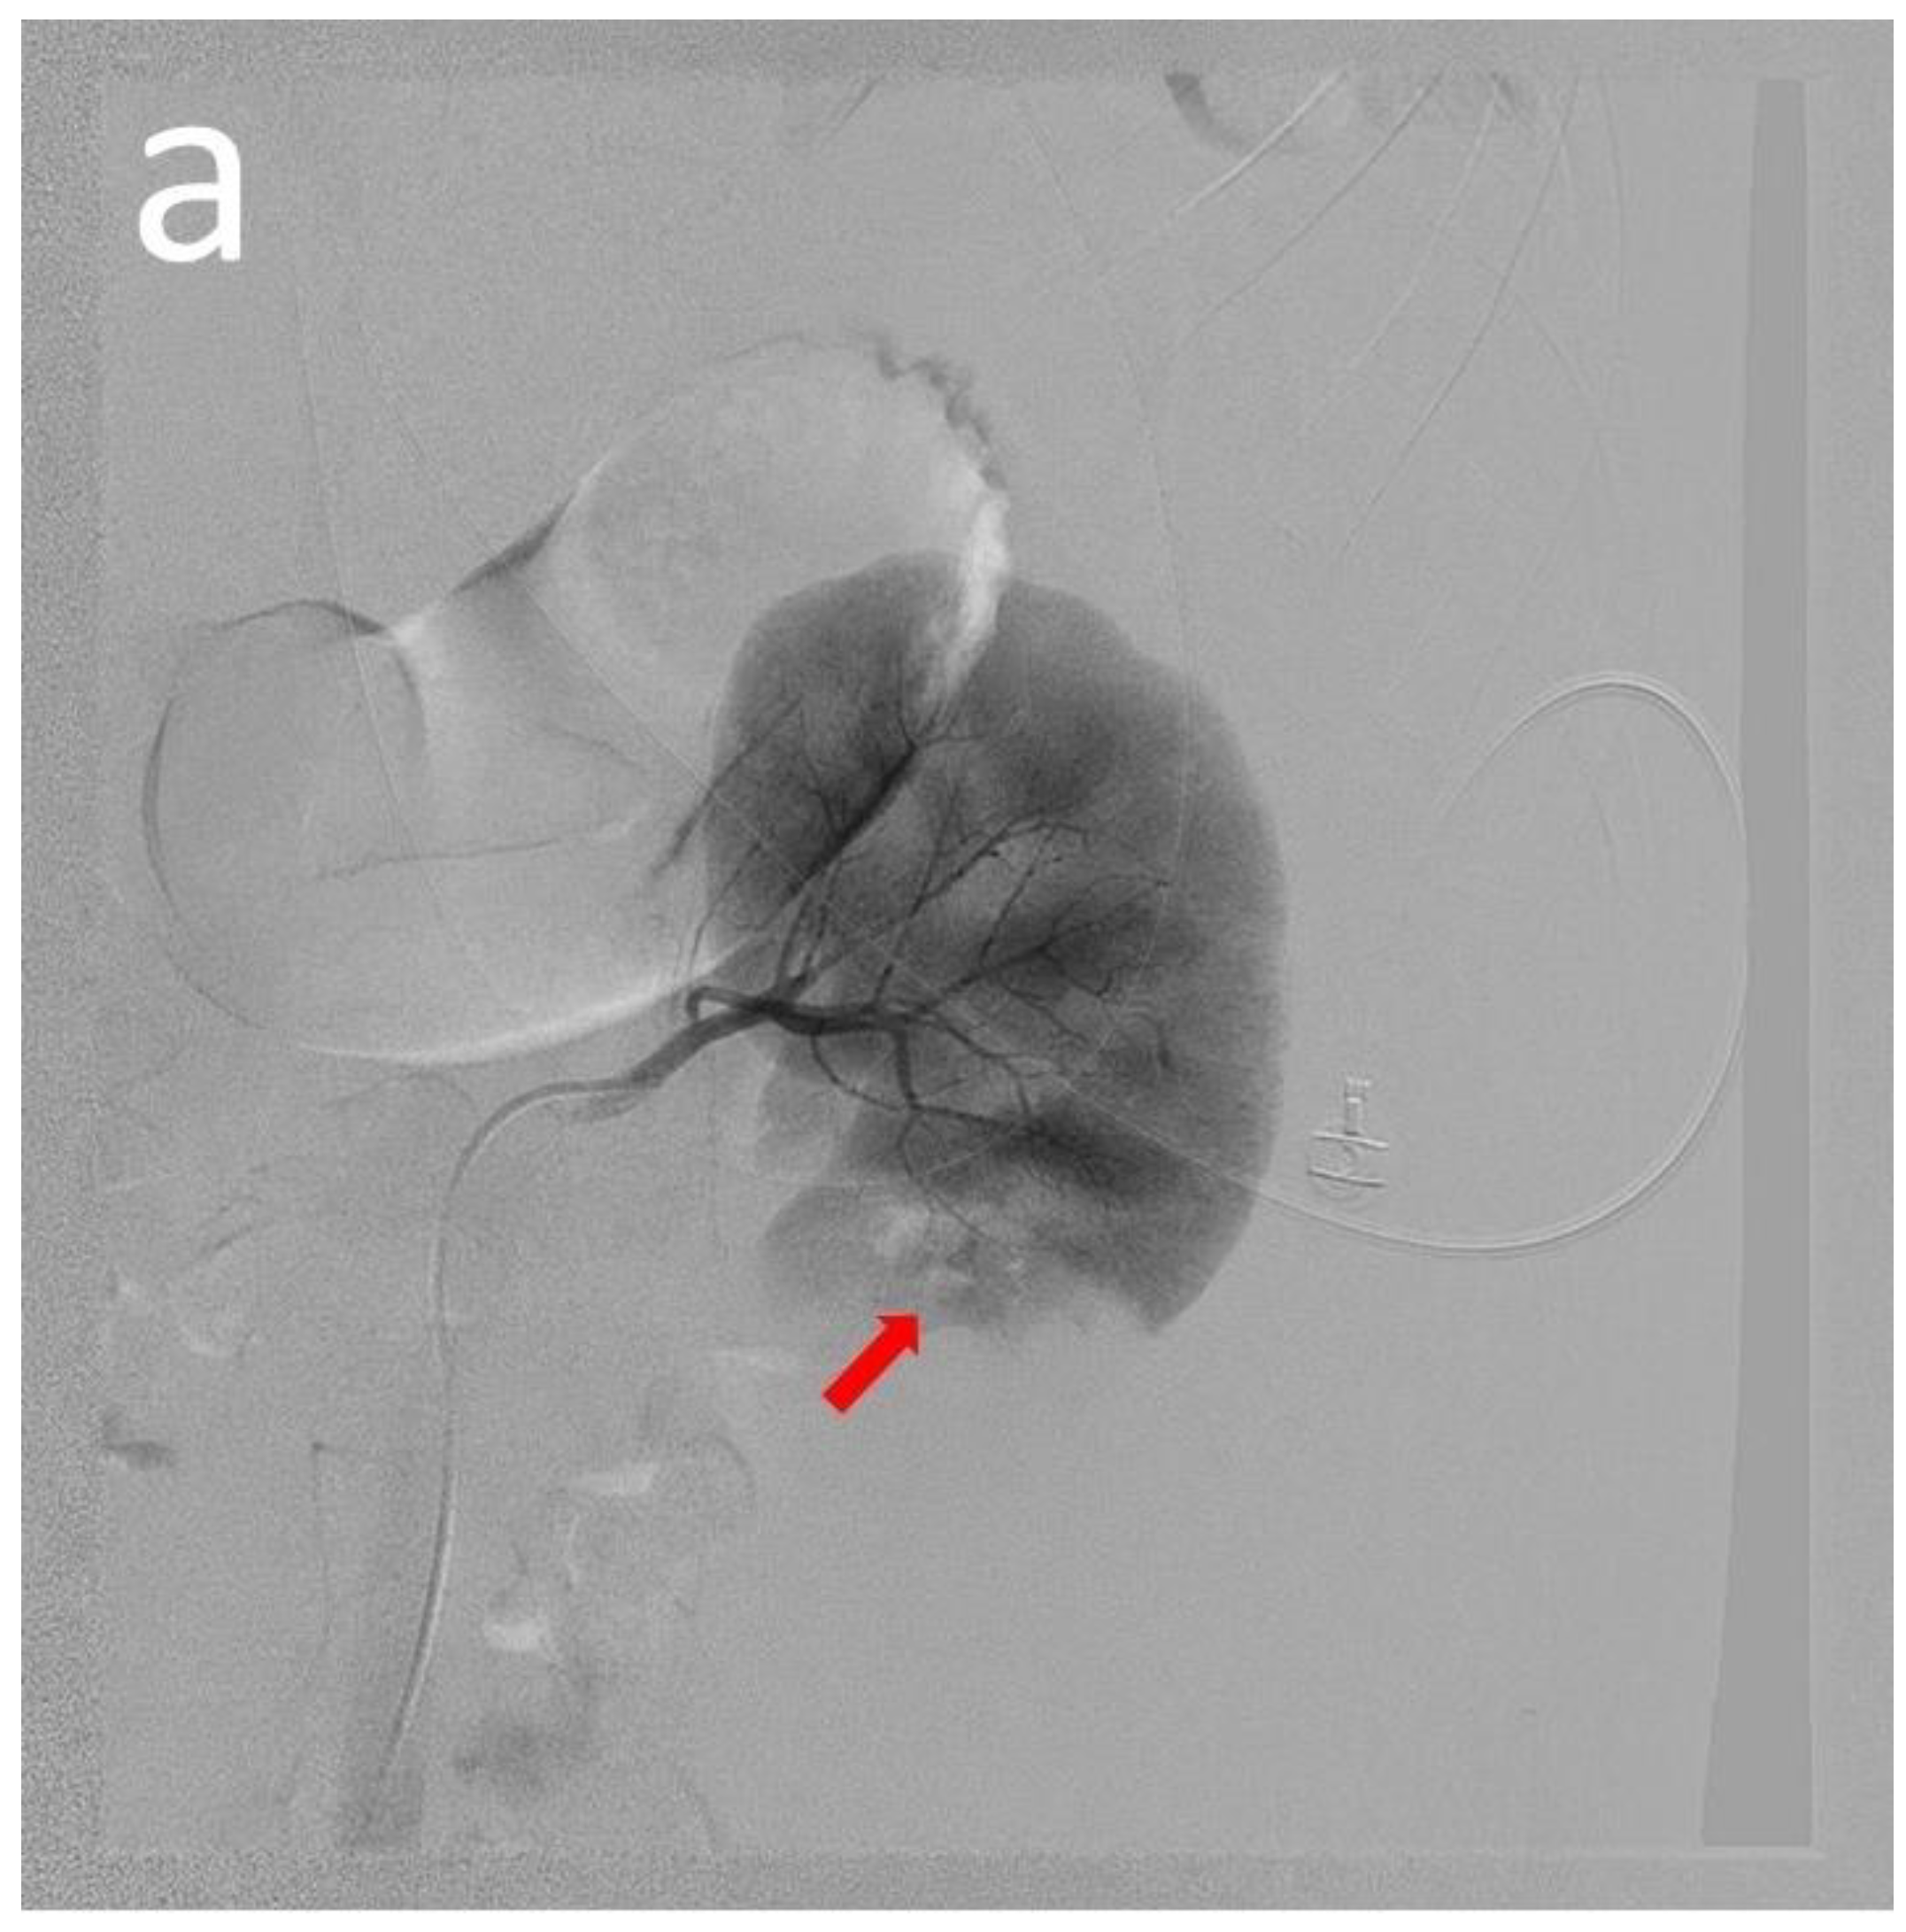

| 13 | Our case | 18 | Male | 12 | Flank pain Anemia(Hb: 6.7 g/dL) | Normal | Normal | CT | Angiodysplasia of the left renal artery & branch of IMA | N/A | Anti-dsDNA antibody Lupus anti-coagulant Anti-cardiolipin IgM | Embolization Steroid | N/A | Alive |